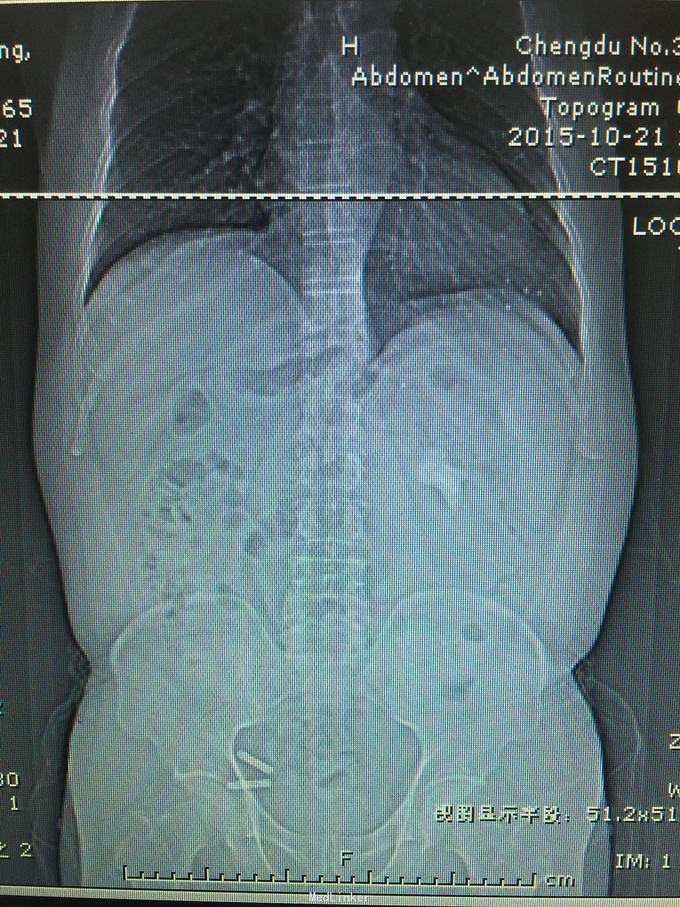

患者男,59岁,因检查发现左肾巨大铸型结石3天入院 病史:患者检查发现左肾结石,无发热,无血尿,无腰痛,食欲,睡眠均正常。

诊断考虑左肾铸型结石。 处理:经皮肾球囊扩张,钬激光加气压弹导碎石,手术顺利,术中术后出血少,术后复查未见结石残留。患者痊愈出院。